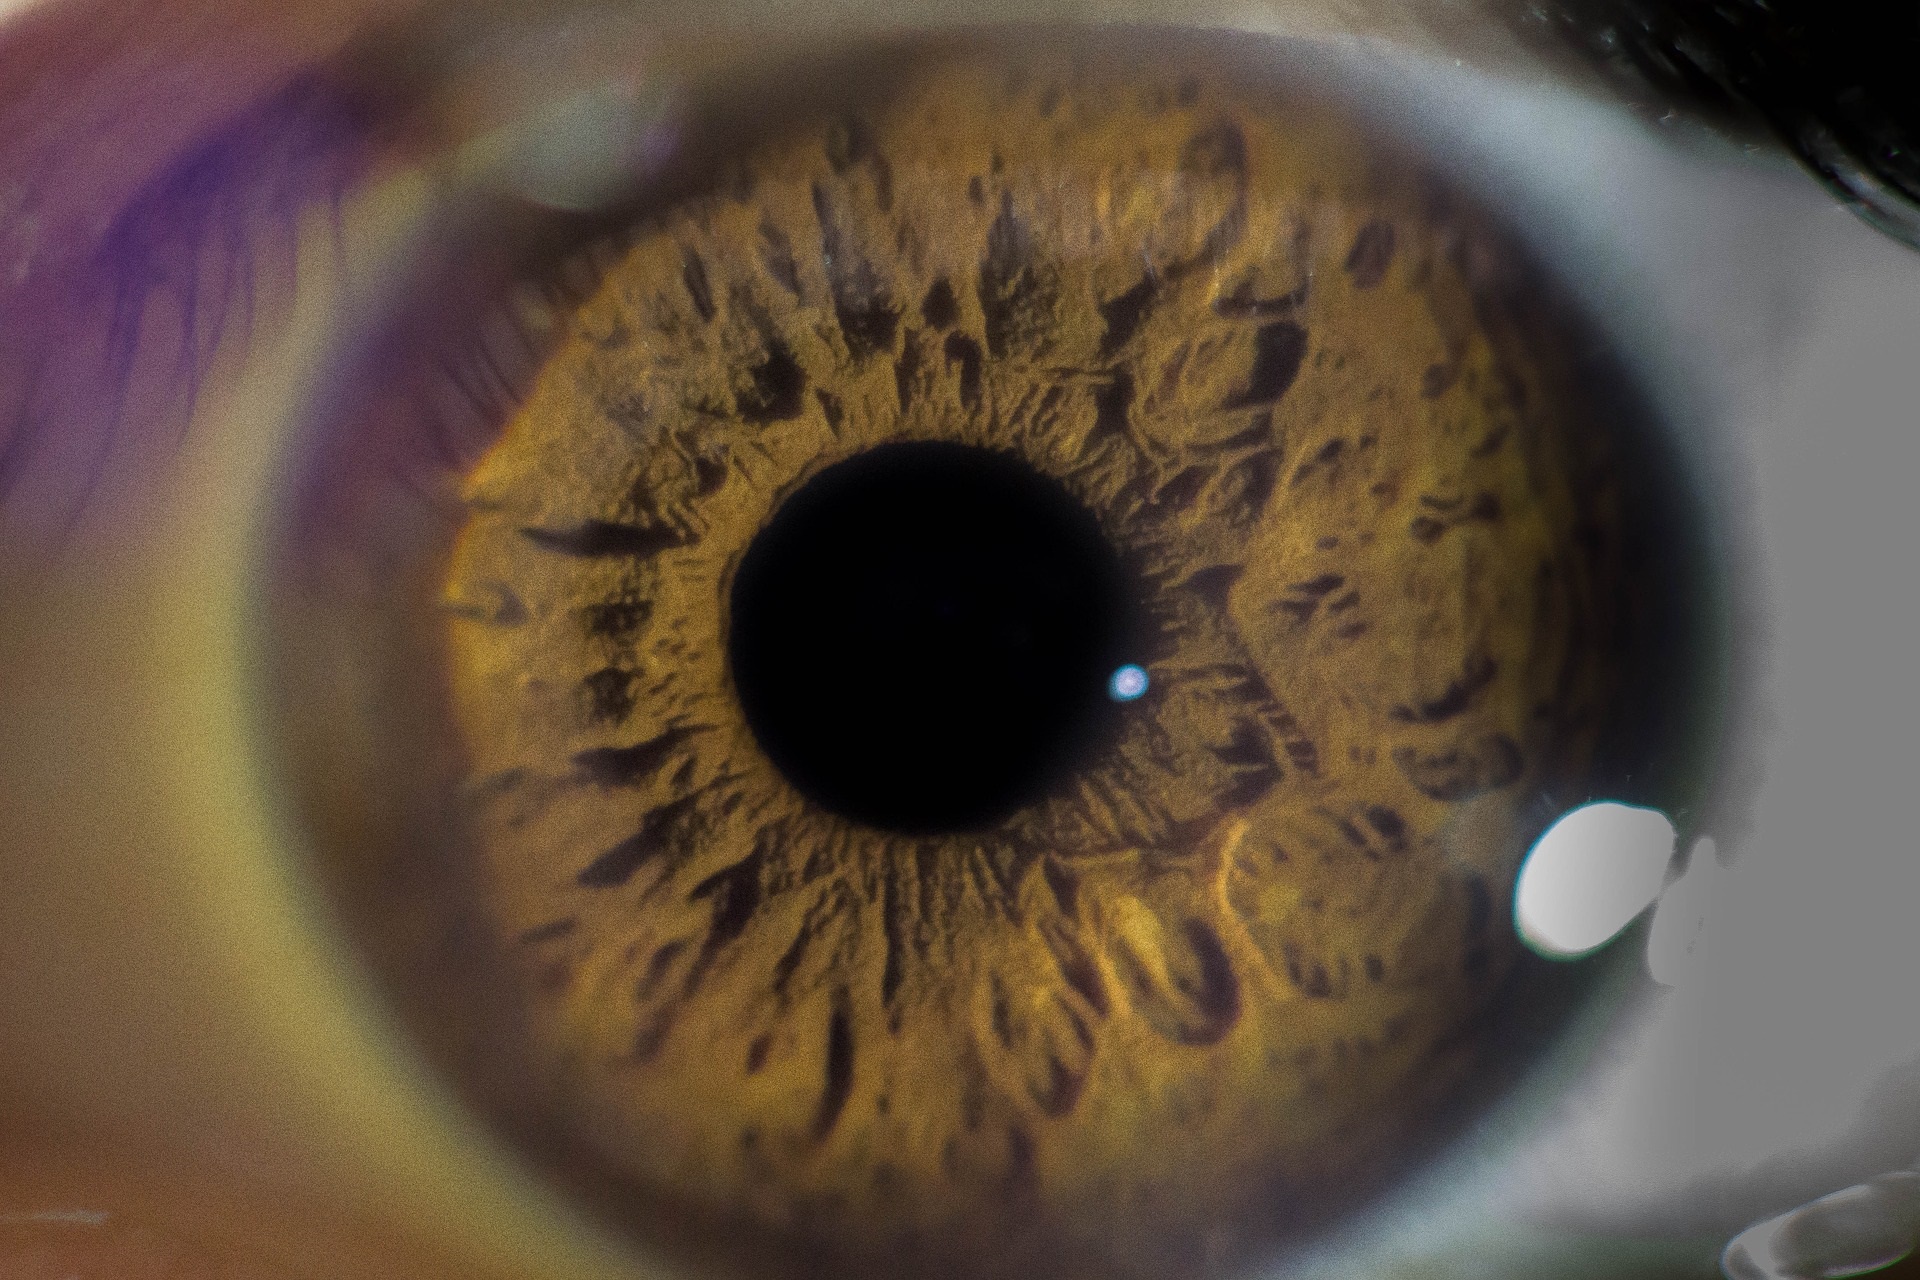

Antes de la entrada de los menores a la escuela, debemos estar muy atentos a las señales de advertencia que pueden significar que existe un problema ocular. Entre los 3 y los 6 años, el niño estará perfeccionando su visión y las habilidades visuales que desarrolló durante los primeros años de vida, por lo que la realización de un examen visual completo antes de que se incorpore a las aulas permitirá tener tiempo suficiente para detectar cualquier anomalía visual que pueda interferir en su rendimiento escolar.

En esta etapa, tal y como indica Ana Belén Cisneros, vicedecana de COOCYL, "se recomienda acudir al óptico-optometrista a los 6 meses, a los 3 años y justo antes de entrar al colegio, incluso si la visión del niño aparentemente es buena para sus progenitores".

Existen pruebas optométricas que se pueden usar en bebés y en niños en edad preescolar que todavía no saben leer y que permiten valorar si presenta alguna ametropía (miopía, hipermetropía, y/o astigmatismo) y una buena visión binocular (descartando ambliopía o estrabismo) o evaluar su visión cromática, motilidad ocular, etc. "En el caso de confirmar cualquier defecto refractivo, el óptico-optometrista prescribirá la mejor solución óptica para el niño o remitirá a otro especialista si fuese necesario", añade Cisneros.